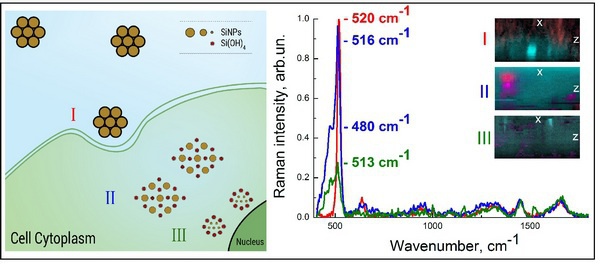

Исследователи из МГУ имени М.В. Ломоносова совместно со своими немецкими коллегами сумели доказать применимость кремниевых наночастиц для диагностики и лечения рака, впервые продемонстрировав их способность эффективно проникать в больные клетки и, выпустив заключенное в них лекарство, быстро разлагаться, не накапливаясь в организме. О деталях своей работы они рассказали в статье, опубликованной в последнем номере журнала Nanomedicine: Nanotechnology, Biology and Medicine.

Слева: Схематическое изображение процессов биодеградации кремниевых наночастиц: (I) локализация наночастиц на мембране клетки; (II), проникновение наночастиц в цитоплазму клетки, сопровождающееся частичной биодеградацией наночастиц; (III) полное растворение кремниевых наночастиц через 10-13 дней их инкубации в клетке. Справа: Спектры комбинационного рассеяния света (рамановские спектры) кремниевых наночастиц, снятые в течение различного времени их инкубации в клеткахMCF-7 (рак молочной железы): 9 ч, 48 ч и 13 дней инкубации изображены красным, синим и зеленым спектром, соответственно. Врезка: соответствующие изображения XZ-сечения клетокMCF-7, культивируемых с наночастицами, полученные с помощью рамановской спектроскопии. Источник: Любовь Осминкина -